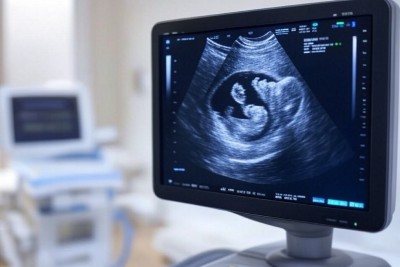

استشارية أمراض النساء تكشف أهمية الأشعة الصوتية في مراحل الحمل

أكدت الدكتورة مها النمر، استشارية أمراض النساء، على الدور المحوري الذي تلعبه الأشعة الصوتية في ضمان سلامة الأم والجنين طوال فترة الحمل. وأوضحت أن هذه التقنية التصويرية غيرinvasive توفر معلومات قيمة للأطباء والأمهات على حد سواء، مما يساعد في الكشف المبكر عن أي مشكلات صحية واتخاذ القرارات المناسبة. في الشهر الثاني من الحمل، يتم إجراء أول فحص صوتي للتأكد من نبض الجنين وتحديد موقع الحمل داخل الرحم، وهو أمر بالغ الأهمية للاطمئنان... |